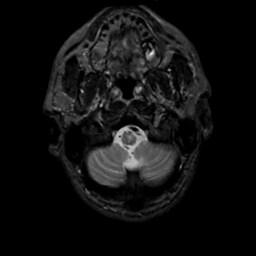

MR Study #1, February 10, 1991 -- Slice #4